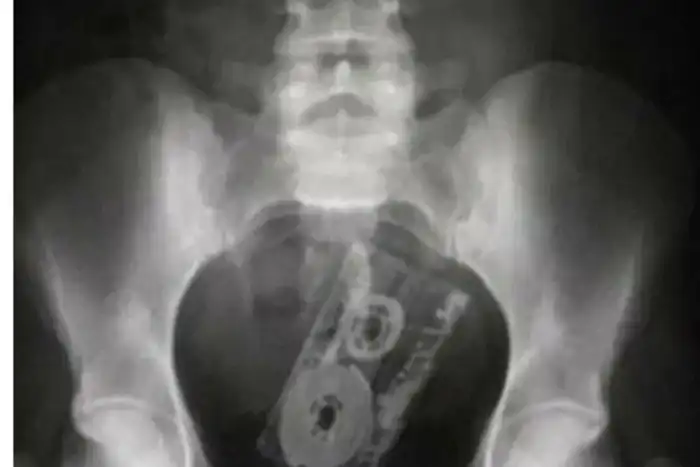

Видимо, человек уж слишком сильно любил эту касету. Об исполнителе остаётся только догадываться...